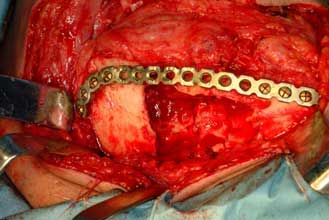

ます。あごの骨を部分的に離断、切除した場合にはチタン製プレートによる固定や骨移植を行い

再建する必要があります。

| エナメル上皮腫切除後(下顎骨) | チタン製プレートによる再建 | |